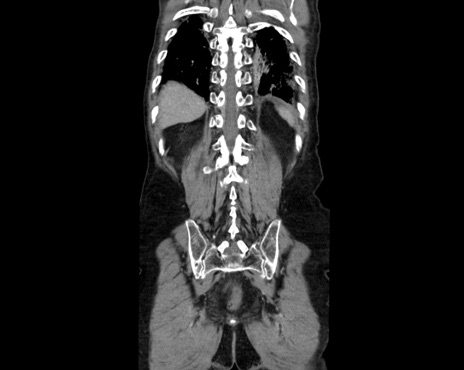

症例26(冠状断像)

【症例】80歳代男性

【主訴】嘔吐

【現病歴】昨晩2回嘔吐あり、今朝になっても嘔吐あり。来院。

【既往歴】胃潰瘍

【身体所見】意識清明、BT 37.6℃、BP 166/95mmHg、HR 100bpm、SpO2 97%、腹部:平坦・軟、腸蠕動音聴取良好、圧痛なし。

【データ】WBC 21900、CRP 1.4